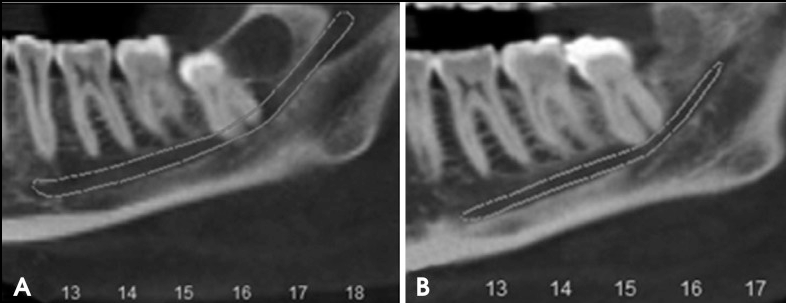

图1 该部位的初始横截面锥形束计算机断层扫描 (CBCT) 图像显示

下颌管与近中 (A) 和远中 (B) 根的曲率之间的接触,如不同的 CBCT 切口所示。

图3 该部位的初始 (A) 和最终 (B) 冠状全景 CBCT 重建图像

显示了下第三磨牙根与下颌下牙槽管之间的关系。